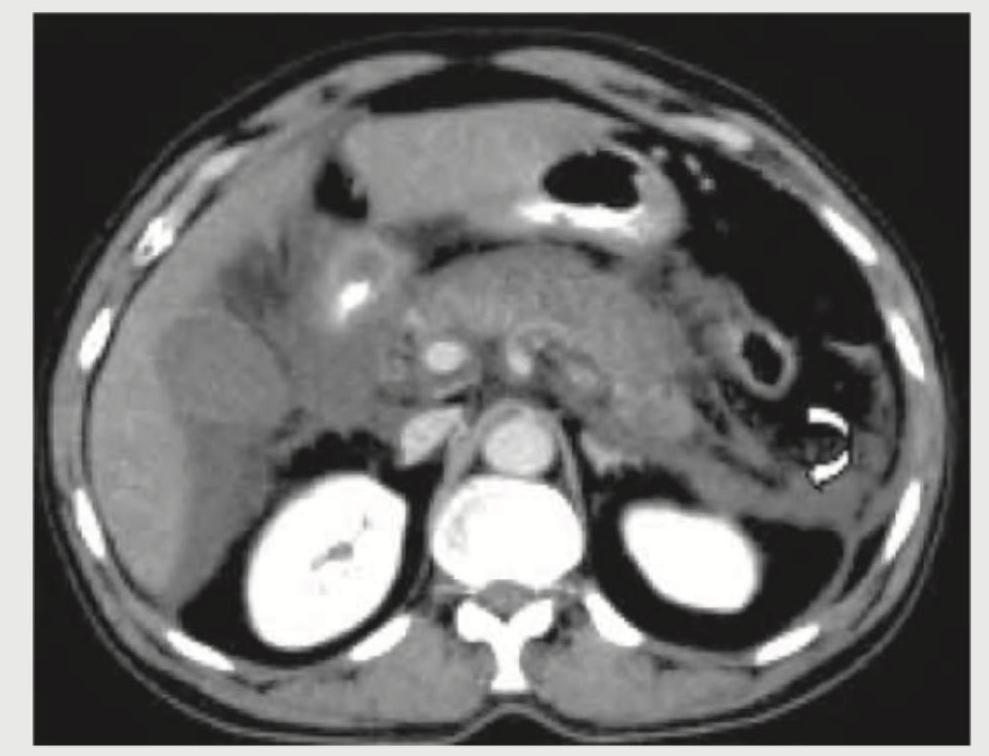

CECT abdomen of a patient with acute abdomen is given below. What is the diagnosis?

Explanation: ***Acute pancreatitis*** - The CECT image shows **peripancreatic fat stranding** and **fluid collection** (highlighted by the arrow), which are classic signs of acute pancreatitis. - The pancreas itself appears **enlarged** and **edematous** with areas of inflammatory changes. *Renal colic* - Renal colic typically presents with a **calculus (kidney stone)** in the ureter or renal pelvis, possibly with **hydronephrosis**. - No such features are visible in the provided image; the kidneys appear unremarkable. *PUD perforation* - A perforated peptic ulcer would show **free air under the diaphragm** on an upright chest X-ray or **free intra-abdominal air** on CT. - The image does not demonstrate any free intra-abdominal air, and the stomach and duodenum do not show signs of perforation. *Rectus sheath hematoma* - A rectus sheath hematoma would present as a **well-defined, high-density collection within the rectus abdominis muscle** or between the muscle and its sheath. - This image shows diffuse retroperitoneal inflammation and fluid collection, not confined to the rectus sheath.